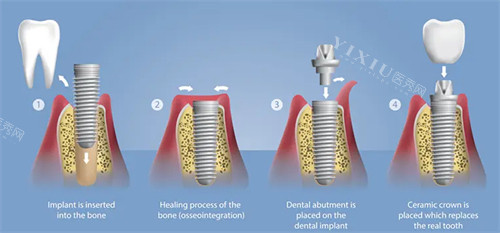

在牙齿治疗方面,该机构针对复杂病例采取多步骤处理方案。例如针对牙列缺损问题,优先评估患者牙槽骨条件,结合咬合关系设计个性化方案,确保功能与美观平衡。对于青少年矫正,通过影像资料分析颌面发育趋势,选择适合的矫治器类型,并在过程中根据牙齿移动情况调整加力方式。

医生团队由多位熟悉种植与正畸领域的从业者组成,定期参与技术交流活动。其中部分成员擅长处理骨量不足的种植病例,通过骨增量技术改善种植条件。正畸方向则涵盖传统托槽与隐形矫正技术,根据患者生活习惯及牙齿情况推荐合适方式。

周边居民反馈中,较多提及种植牙的稳定性与矫正成效的自然呈现。有患者表示,半口种植后咀嚼功能明显改善,定期维护建议实用。正畸实例中,多位青少年家长认可矫正后的咬合调整成效。前台人员对老年患者的耐心沟通态度也常被提及。

该机构在复杂牙病处理上形成特色,如针对牙周病患者的种植前处理,通过系统治疗控制炎症后再进行手术。对于多颗牙缺失病例,采用分段种植方案降低手术创伤。在美学修复领域,重视前牙形态与面部比例协调性,通过比色板选择接近天然牙的修复体颜色。